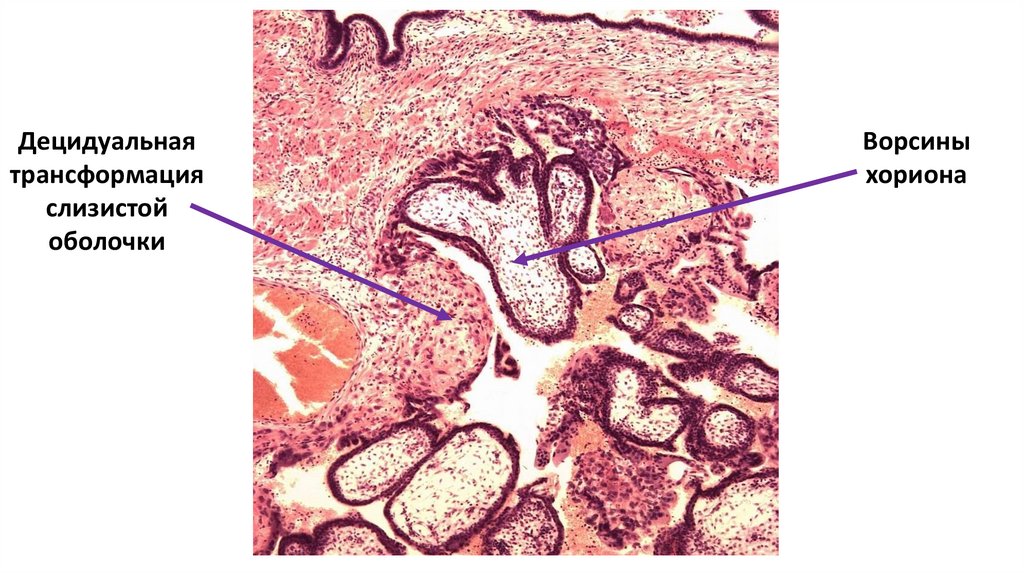

Децидуальная

трансформация

слизистой

оболочки

Ворсины

хориона